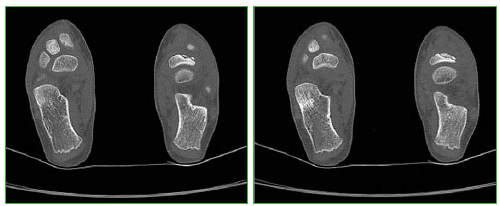

Acceso mediante suscripción PDF Acceso mediante suscripción PDF_EN (English) Acceso mediante suscripción Figura 1 Acceso mediante suscripción Figura 2 Acceso mediante suscripción Figura 3 Acceso mediante suscripción Figura 4 Acceso mediante suscripción Figura 5 Acceso mediante suscripción Figura 6 Acceso mediante suscripción HTML